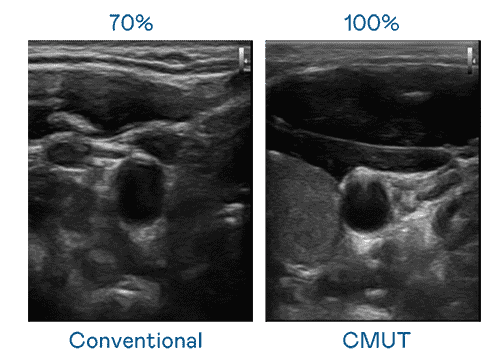

CMUT 技术是一种用电容式微机电元件来产生超音波讯号的技术。。。。与传统 PZT 压电式技术相比,,,,CMUT 频宽增加 30%,,更宽频的超音波讯号让影像解析度大幅提升,,是实现高影像品质医疗超音波扫描、、促进精准医疗发展的关键技术。。。

大频宽带来超清晰影像

超音波影像的解析度高低,,首先取决于探头能发出的讯号频宽。。龙门国际 CMUT 可提供高清晰的超音波讯号,,,提供高频宽、、高灵敏度、、影像纹理细节更高的超音波影像,,协助医护人员缩短影像判读时间及利用精准的医疗影像进行诊断。。